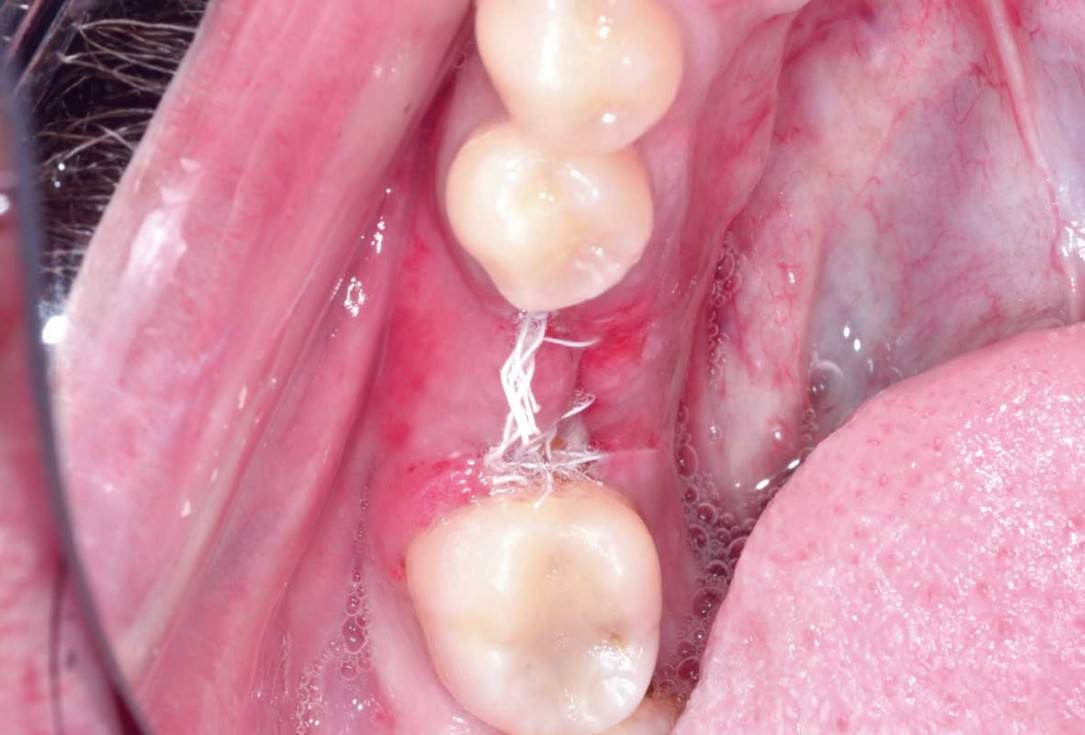

01/25 - Initial situation with broken tooth 46Immediate implant placement and peri-implant bone augmentation with cerabone® plus - Dr. R. Block Veras